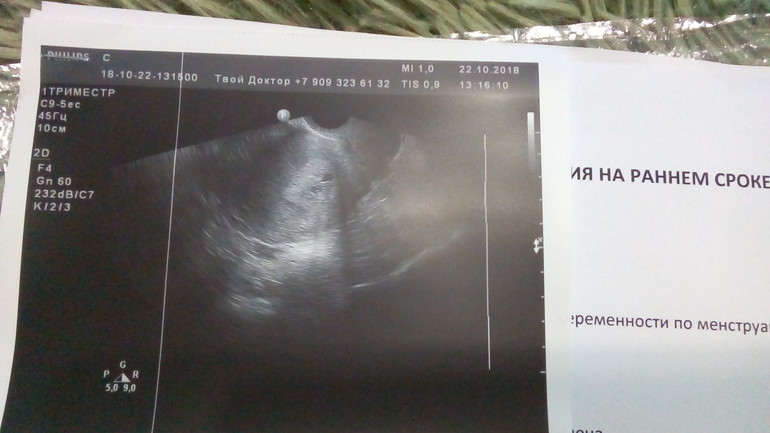

Беременность- 1 триместр ( только до 10 недель)УЗИ по последним месячным 5 недель и 6 дней

Узистка ошиблась, в результате УЗИ написала, что эмбрион визуализируется, эмбриона пока не видно, но хорошо виден желточный мешочек 2,5 мм, она сказала, что это хороший признак, что эмбрион будет позже виден, так как он мал ещё. Плодное яйцо отстаёт по сроку от месячных на 1,5 недели. Возможно отстаёт из-за низкого прогестерона и потом догонит свой срок. Ещё слышала случаи, что Плодное яйцо может где то там задержаться и поэтому оно меньше по размеру. Такое малюсенькое, всего 4 мм и жёлтое тело маленькое 11 мм, вот и прог низкий из-за него. Хорошо, что я увеличила дозу дюфастона. Будем смотреть на УЗИ через недельку.